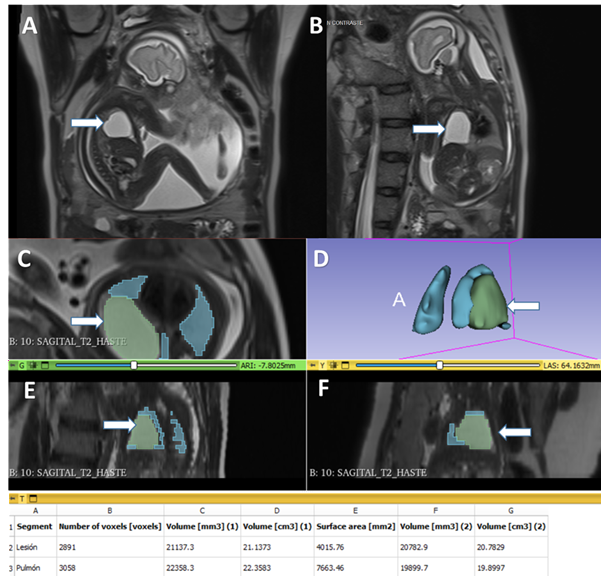

Differential diagnosis included bronchogenic cyst, congenital pulmonary airway malformation and pulmonary sequestration. Mr without paramagnetic contrast was performed at 28 weeks. It demonstrated increased size of the lesion (33.8 x 48.5 x 26.6mm) with a volume of 21cc. The calculated remnant pulmonary volume on both thoracic cavities was 22.3cc. This value corresponded to 41.3% of the expected percentage for this gestational age (figure 4). Mediastinal shift persisted and no signs of fetal hydrops were found. The mr study did not show other related malformations.

Figure 4: magnetic resonance imaging without contrast at 28 weeks, showing t2-weighted images in a (sagittal) b(coronal) view of the fetus. It is possible to recognize a hyperintense round lesion in the topography of the right lung (arrows). D, e and f. Total fetal lung volumetry, residual and of the cystic lesion.